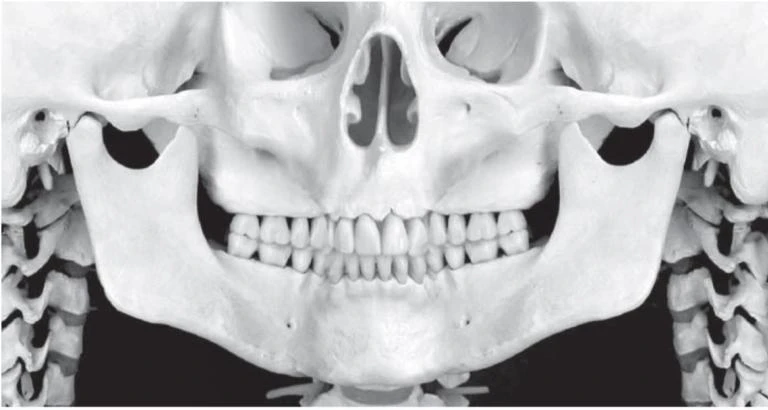

Nhà lâm sàng nên quan sát hình ảnh như thể nhìn vào bệnh nhân, với những cấu trúc bên phải của bệnh nhân sẽ nằm phía bên trái của người xem ảnh. Vì vậy hình ảnh được hiển thị cùng chiều như với hình ảnh trên phim quanh chóp và phim cánh cắn, giúp việc phân tích phim dễ dàng hơn. Điều cực kỳ quan trọng là nhận ra các mặt phẳng của bệnh nhân thể hiện trên những phần khác nhau của phim toàn cảnh. Hình ảnh trên phim toàn cảnh thật ra gồm ba hình ảnh: hình ảnh bên phải và bên trái phía sau răng nanh và một hình ảnh theo chiều trước sau từ phía trước cho đến vị trí răng nanh. Phần phía trước cũng bị biến dạng nhiều nhất và bị chồng với những cấu trúc từ đốt sống cổ. Vì vậy, phương pháp tiếp cận bằng cách hình dung phim toàn cảnh gồm hai phần hình ảnh chụp phía bên quanh một phần ảnh chụp theo chiều trước sau ở giữa, một loại hình chiếu Mercator của mặt giữa và mặt dưới. Phương pháp hình dung này cho phim toàn cảnh được mình hoạ ở hình bên dưới.